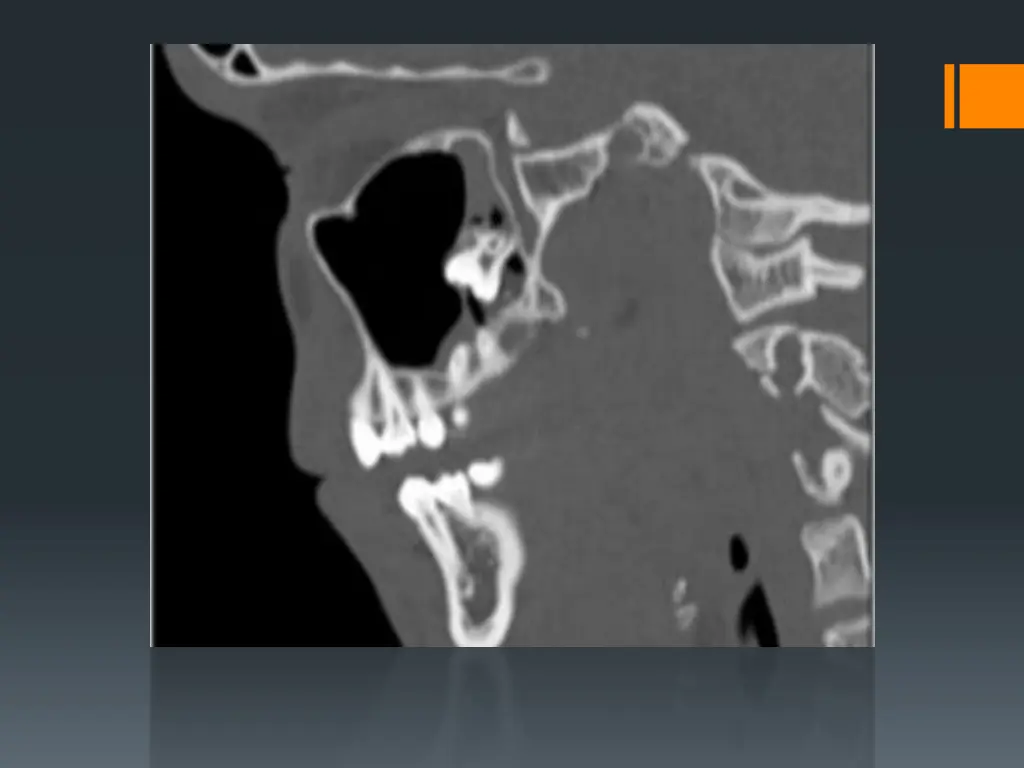

C- Maxillary tuberosity fracture: Sometime the tuberosity is completely fractured when we try to remove maxillary 3rd or 2nd molar. Fracture of maxillary tuberosity may lead to a wide opening into the antrum called Oro-antrum communication with irregular tearing in the covering soft tissue lead to profuse bleeding and post-operatively may lead to difficulties in the retention of upper denture. This complication might occur if : 1-the molar tooth to be extracted is isolated and subjected to full force of bite leading to sclerosis of the surrounding bone 2-due to downward extension of the maxillary sinus to the nearby edentulous alveolar bone or due to large abnormal size of the maxillary sinus extended to involve the tuberosity. 3-the use of excessive force or wrong positioning of the elevator in the extraction of upper 3rd molars

So the extraction with high force without direct vision on the retained root may lead to such complications, also retained root may be displaced into the maxillary antrum during the extraction of upper molar or sometimes premolar teeth especially palatal root of upper molar teeth. The presence of large antrum or the use of excessive force during extraction or due to pathological conditions like periapical pathology. All these factors may assist or predispose to such complication, so pre-operative radiograph and clinical evaluation may assist in the prevention of such complication.